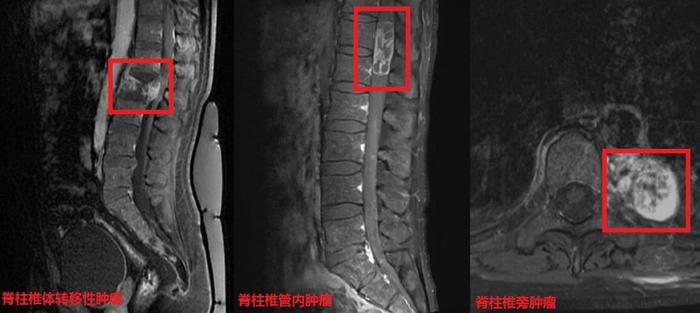

最常见的脊柱肿瘤脊柱转移瘤

图片尺寸4060x1562